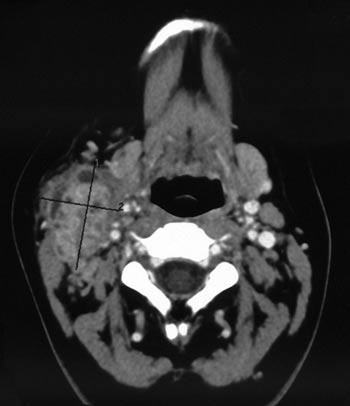

Pasient 1. En 20-årig kvinne ble henvist til spesialist etter fem uker med influensaliknende symptomer og progredierende voksende tumor på høyre side av halsen, etter hvert med involvering av overliggende hud. Hun var blitt penicillinbehandlet for antatt halsinfeksjon, uten nevneverdig effekt. Monospot og streptest var negative, og CRP var maksimalt 77 mg/l. Det var normale forhold i munnhule, oro- og hypopharynx, og ingen cystevæske ved punksjonscytologi. Hun ble henvist med spørsmål om abscess. Ultralydundersøkelse viste en 4 cm stor tumor med en sentral lavekkogen oppklaring samt multiple forstørrede lymfeknuter i tilslutning til lesjonen. CT-undersøkelse av halsen (fig 1) viste en stor multicystisk ekspansjon på 4,5 cm med uskarp avgrensning medialt for m. sternocleidoideus. Malignitet kunne ikke utelukkes. Hun ble behandlet med aminopenicillin og metronidazol intravenøst – uten effekt. Det var ikke antistoffer mot HIV-1 eller HIV-2, Mycoplasma pneumoniae, Yersinia enterocolitica O3, Toxoplasma gondii eller Bartonella henselae. Blodprøver ved innkomst viste leukocytter 12,2 · 10⁹/l og CRP 43 mg/l, øvrige prøver var normale. Hun ble operert med drenasje av en lobulert abscess. Undersøkelse for tuberkulose med PCR, direkte mikroskopi og dyrking var negativ. Histologisk undersøkelse viste kronisk betennelse og nekrose. PCR-undersøkelse for F tularensis utført på biopsimaterialet var positiv. Ved serologisk analyse var det funn forenlig med en aktuell F tularensis-infeksjon (agglutinasjonstiter 1 024 samt høye IgM- og IgG-titre ved enzymimmunoassay (EIA)). Hun fikk ciprofloksacin 500 mg to ganger daglig i ti dager og ble raskt symptomfri.